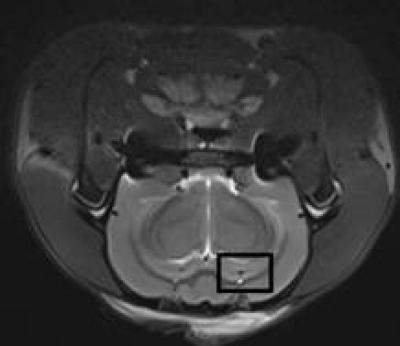

The MRI T2-weighted images showed no significant difference in rats 2 weeks after Alzheimer's disease was induced.

(Photo Credit: Neural Regeneration Research)